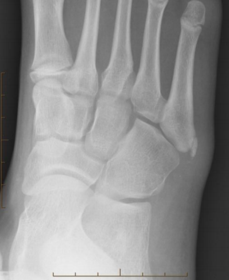

What disease is this? What do the arrows indicate? | Gout Arrows = 'punched out' erosions |